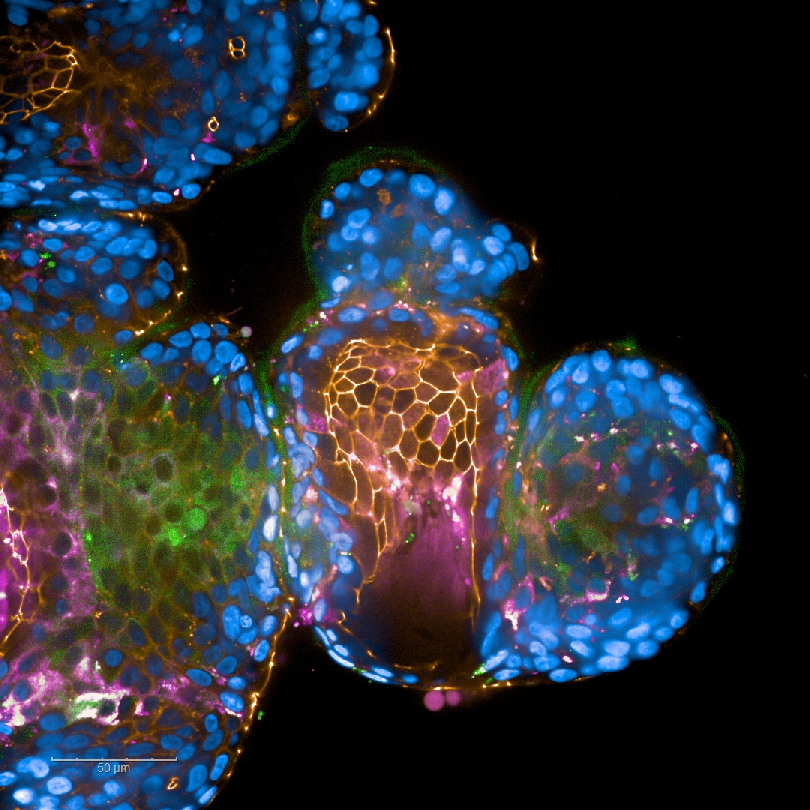

Highly differentiated cell culture models are also being developed by Wilflingseder’s group, in order to allow research into the initial interactions between various pathogens (HIV-1, Aspergillus, Chlamydia) in the acute phase of infection. The established human 3D mucous membrane model is very promising in this context. The in vitro system allows detailed analyses of HIV-1 and HIV-2 with molecules and enzymes of an intact, complex mucous membrane and the development of novel therapeutic approaches. The mucosal/immune model is funded with a grant from the National Institutes of Health (NIH). Together with our American colleague, Thomas J. Hope from Northwestern University in Chicago, the behaviour of HIV-neutralising antibodies in this human mucosal model will be investigated, in order to pave the way for new vaccination strategies against HIV.

The respiratory barrier/immune model has been optimised in recent years as part of an ÖNB project. This 3D model and differentiated apical-out lung organoids are applied in further studies using pathogenic fungi (in cooperation with CL-F.) or SARS-CoV-2 (project leader: WP > COVID19 project).

- Chandorkar P, Posch W, Zaderer V, Blatzer M, Steger M, Ammann CG, Binder U, Hermann M, Hörtnagl P, Lass-Flörl C, Wilflingseder D: Fast-track development of an in vitro 3D lung/immune cell model to study Aspergillus Sci Rep. doi: 10.1038/s41598-017-11271-4. 2017 Sep 14;7(1):11644.